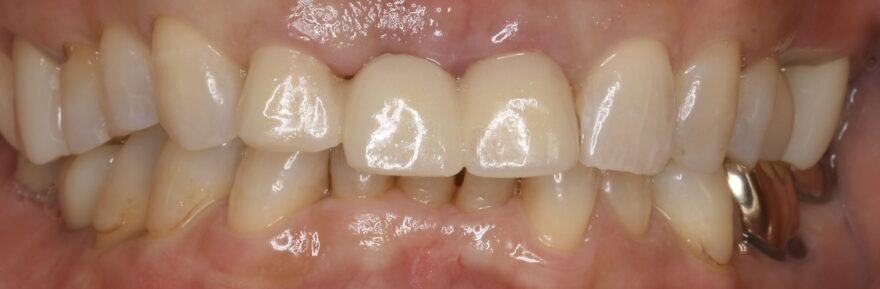

初診時口腔内写真

かかりつけの医院さんで、前歯のインプラント治療はできないと言われての、当院受診でした。

治療後の口腔内写真

なおインプラントの両サイドにはセラミック歯を被せてます。